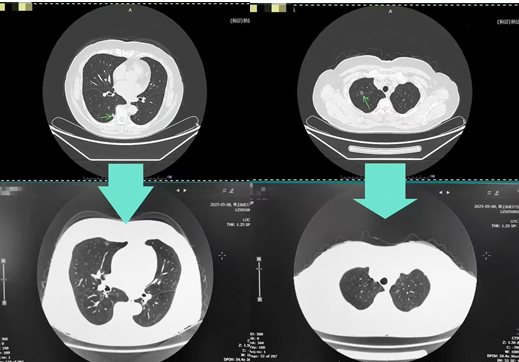

经过中医科 1 个月的精心调理,刘阿姨的咳嗽、胸闷及乏力症状得到了显著缓解。4 个月后复查肺部 CT,右肺结节较前明显缩小,部分结节消失。面对这一喜人的转变,刘阿姨激动不已:“困扰了我一年多的咳嗽终于好了,精神也好了,肺结节也消了大半,终于可以睡个安稳觉了。”(文:李倩)